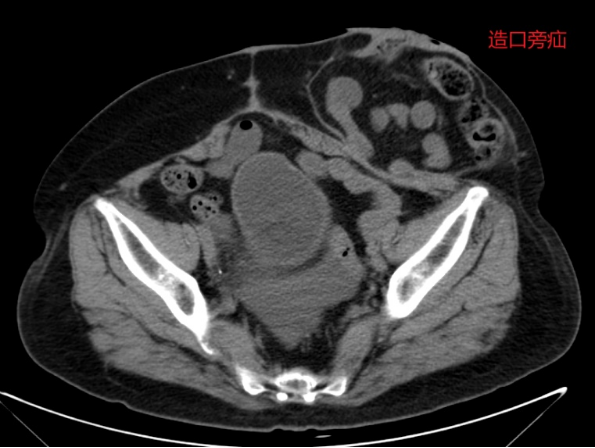

病情简述:59 岁女性,宫颈癌术后第 3 天并发乙状结肠瘘。

诊疗破局: 团队急诊行腹腔镜手术控制感染并造口。半年后患者要求还纳造口,术前发现合并造口旁疝。经周密规划,在一次腹腔镜手术中同时完成「造口还纳」与「疝修补术」,避免了两次手术创伤。

技术体现: 从急诊处理到远期重建,微创外科贯穿始终,体现了系统性治疗的前瞻性。